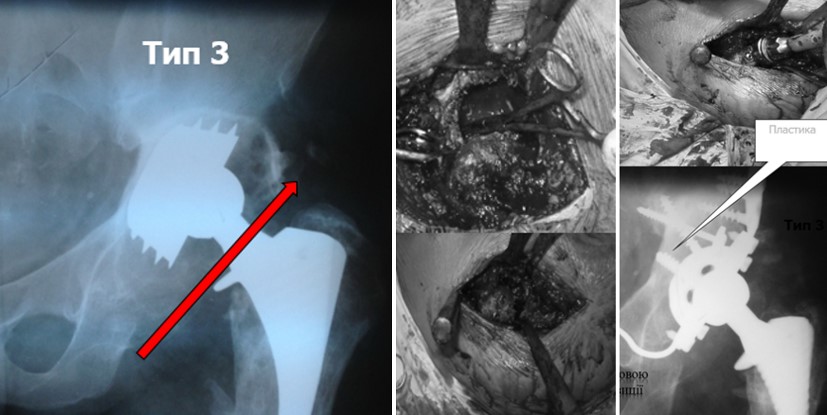

ІІІ тип

В своїй роботі ми класифікацією кісткових дефектів ложе нестабільнокористувалисяго протеза колінного суглоба за AORI (Anderson Orthopaedic Research Institute, USA), 1997 де автори виділяють 3 типа кісткових дефектів

Тип 3 – дефіцит кістки (deficient metaphyseal segment) – характеризується вираженою втратою губчастої і кортикальної кісткової маси метаепіфіза, без компенсації якої неможливе створення опори для компонентів ревізіційного імплантату і відновлення нормального рівня суглобової лінії. Дефекти частіше поширюються до надвиростків і вище на стегнової кістці або до горбистості і нижче на великогомілковій кістці. (F3 А та F3 Б – для стегнової і Т3 А та Т3 Б– для великогомілкової кісток)